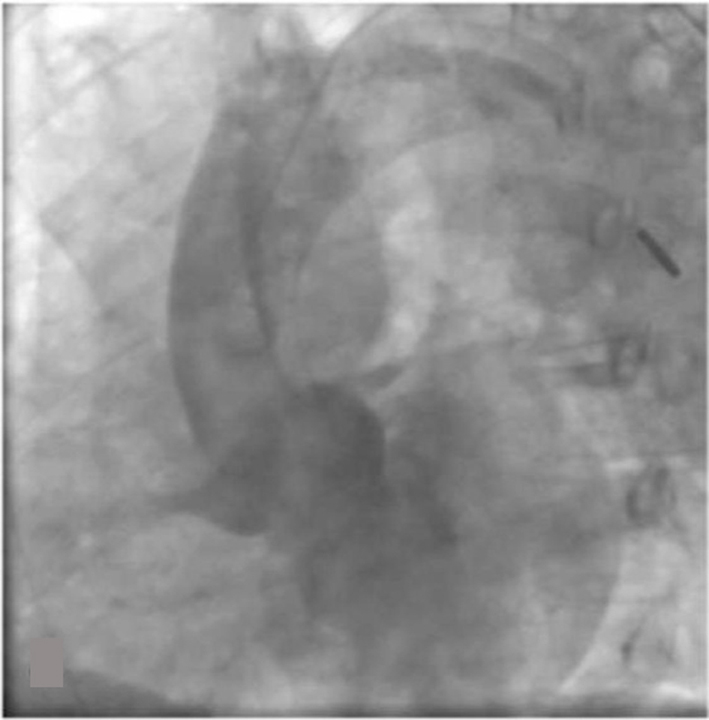

In the cath lab the right radial artery was cannulated with a 6-French sheath. A Launcher EBU 3.5 guide catheter (Medtronic, Minneapolis, MN) was used to engage the left coronary ostium. Coronary angiogram revealed a subtotal occlusion of the left main coronary artery (Fig. 2). A Runthrough wire (Terumo Medical Corporation, Somerset, NJ) was utilized to cross the lesion and a 3.0 x 15 mm Emerge balloon (Boston Scientific, Natick, MA) was used for initial angioplasty. Since patient became hypotensive, intraaortic balloon pump was placed from the right femoral artery. Two 4.0 × 12 mm Promus Element Everolimus-Eluting stents (Boston Scientific, Natick, MA) were deployed in the left main artery with good angiographic result (Fig. 3). Intravascular ultrasound (IVUS) was performed to confirm the stent expansion.

Figure 2. Subtotal occlusion of the left main coronary artery. |